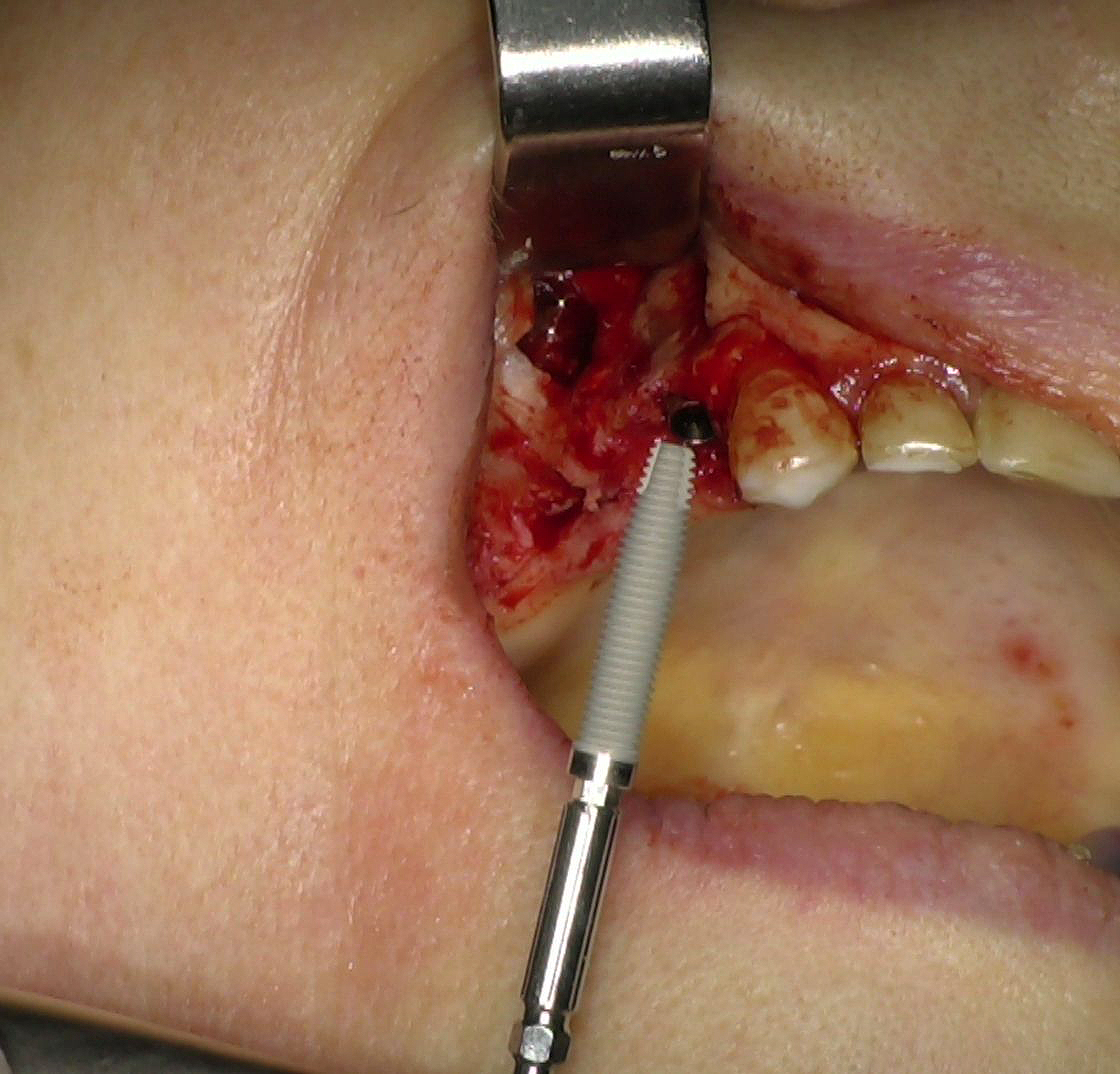

L'intervento chirurgico è stato eseguito in anestesia locali. Dopo il sollevamento di un lembo musopeiosteo a tutto spessore per esporre il mascellare, nei settori anteriori si è proceduto con la preparazione dei siti implantari secondo protocollo convenzionale. Gli impianti IS+ sono stati quindi posizionati (Fig. 2), ottenendo una buona stabilità primaria grazie alla presenza di un adeguato volume di osso residuo.

Fig. 2 - Impianti IS+